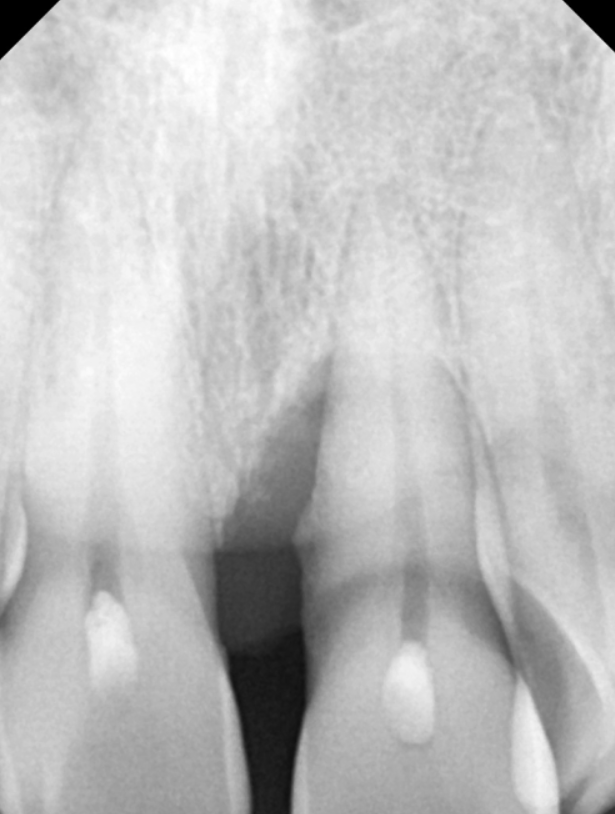

정확한 상태 확인을 위해 엑스레이 촬영과 검사를 진행한 결과,

치석으로 인해 잇몸병이 진행되면서

잇몸뼈가 일부 녹아 있는 상태였습니다.

230413 / 230417

잇몸뼈가 줄어들면

치아를 받쳐주던 힘이 약해집니다.

그 결과 치아가 제자리에서 점점 내려오고,

치아가 길어 보이게 됩니다.